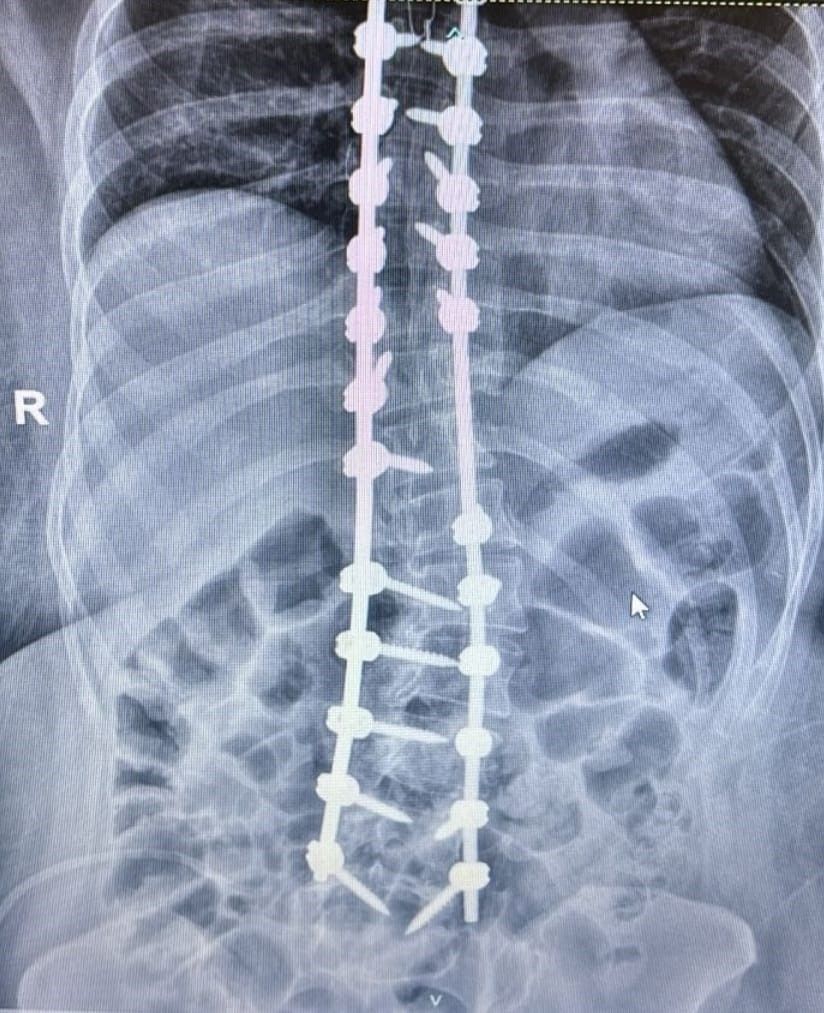

La cirugía, que representa un salto cualitativo respecto a la tradicional cirugía “a cielo abierto”, permite una recuperación más rápida y segura para el paciente. Gracias al uso de un sistema de navegación computarizado, se logró colocar tornillos con mayor precisión y con una exposición significativamente menor a los rayos X.

“En el Hospital Escuela hicimos una intervención con una técnica innovadora con tecnología. A través de la navegación se realiza la colocación de tornillos, lo que mejora la precisión, reduce la exposición a la radiación y permite una mejor corrección de las curvas de la columna”, explicó el Dr. Reble.

La escoliosis en una deformidad en el plano coronal ( frente del paciente ) en forma de S y en algunos casos, implicar rotación vertebral. Si bien no todas las curvaturas generan complicaciones, las más severas pueden provocar dolor, afectar la postura y comprometer funciones de órganos vitales como el corazón, los pulmones y el sistema digestivo.

El tratamiento de la escoliosis depende del grado de curvatura. En casos leves (hasta 25 grados), se realiza un seguimiento expectante. Entre 25 a 40 grados si es esqueléticamente inmadura el paciente se indica el uso de corset. Cuando las curvas superan los 40 grados, como en el caso tratado en el Madariaga, se indica la resolución quirúrgica.

“La escoliosis severa se visualiza a través de radiografías completas de la columna.

Cuando la curvatura supera los 40 grados, evaluamos la intervención quirúrgica”, detalló Reble.